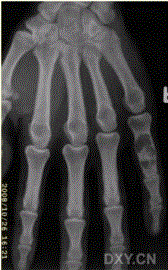

问题 患者男,28岁,偶尔发现右手第5近节指骨肿胀。查体:右手掌肿块,质硬,无明显压痛,无发热。进行了右手X线平片CT检查(下图)。 病变发生部位在

选项 A.近节指骨骨端 B.近节指骨骨干 C.近节指骨骨骺 D.近节指骨干骺端 E.指骨周围软组织

答案 B